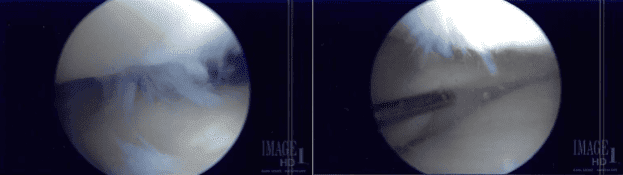

Se construyó un portal lateral. Se introdujo el endoscopio y se examinó la rodilla. Había artritis patelofemoral. El endoscopio se introdujo en el compartimento medial. El portal de entrada medial se realizó utilizando una aguja espinal.

Se examinó el menisco medial y se encontró que el margen se deshilachaba en el margen, así como degeneración de la superficie inferior del cuerno posterior del menisco medial.

La afeitadora se usaba para eliminar todo el deshilachado y equilibrar el menisco. El endoscopio se introdujo en el compartimento lateral, donde también se encontró que el menisco lateral estaba intacto.

Hubo artritis del cóndilo femoral de etapa II a III, que se limpó con una afeitadora. No hubo daño condral en el cóndilo femoral lateral.

El endoscopio se introdujo en la articulación patelofemoral, donde había artritis de grado 3 a 4, y sobre la troclea, de grado 1 a grado 2 sobre la superficie posterior de la rótula.

Se usaban afeitadores y ponches para extraer todo el cartílago de la tróclea así como de la rótula. El cartílago se equilibró a un margen estable. La rodilla fue examinada de nuevo y se encontró adecuadamente desbridada.

La rodilla fue abundantemente irrigada con solución fisiológica normal. Se guardaron las imágenes finales. Se retiró el endoscopio y se cerró la incisión usando nylon #4-0.